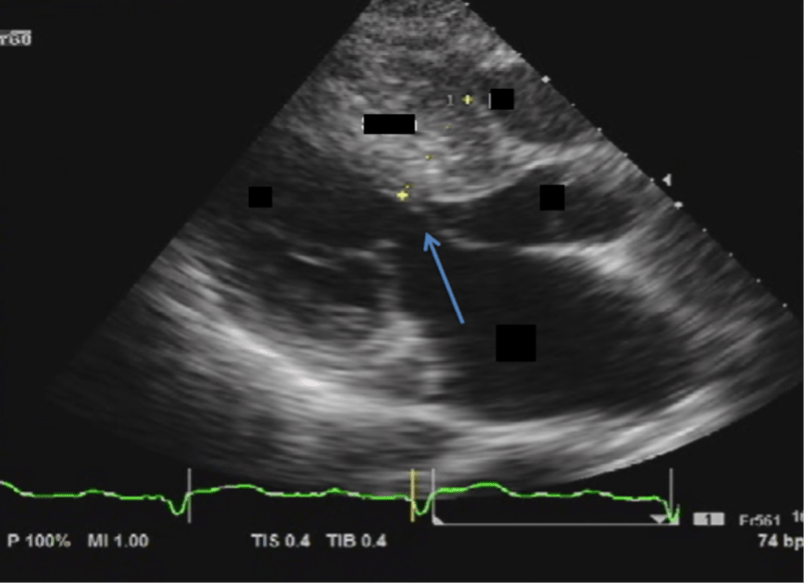

Dynamic condition shown at the blue arrow

What is systolic anterior motion (SAM)?